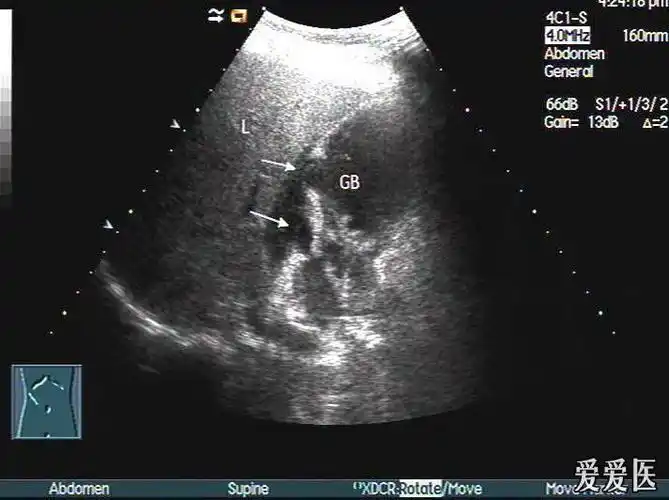

考虑急性坏疽性胆囊炎伴穿孔可能——zengerya - 超声医学讨论版